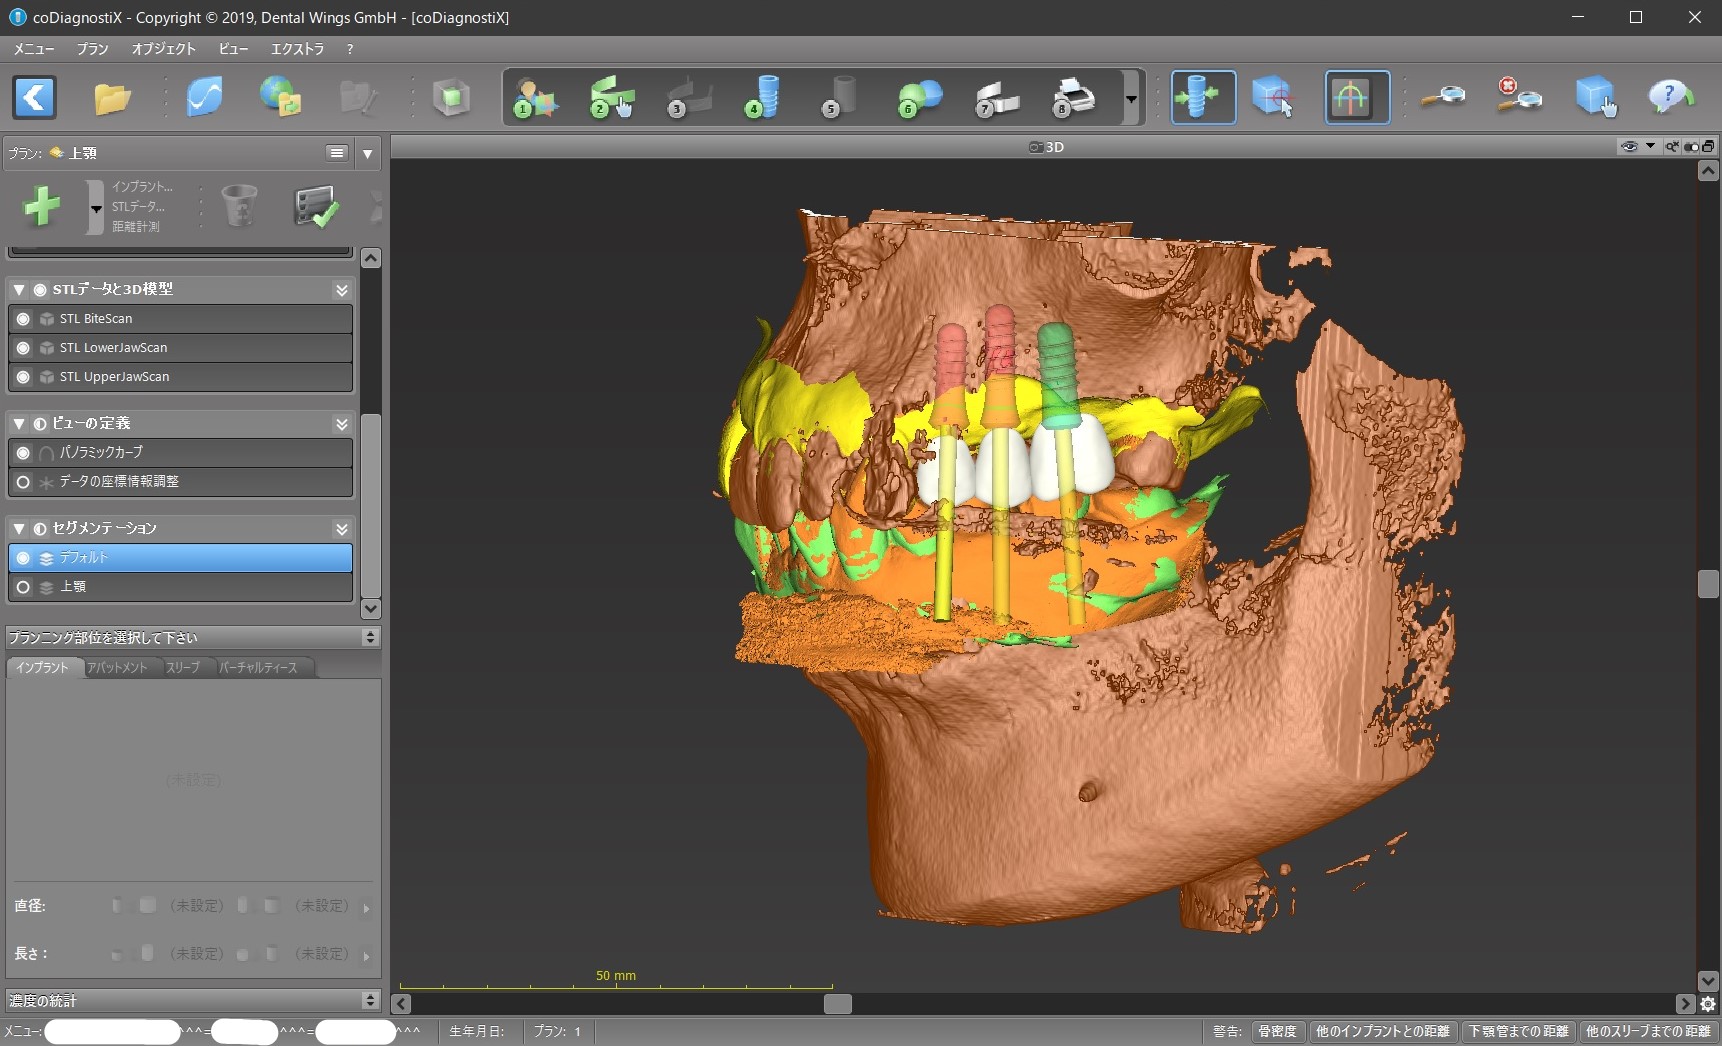

そのシュミレーション・ソフト上で、バーチャル・ティースを設計しました。

バーチャル・ティース

上下の歯のかみ合わせが分かりやすいように、CTの骨のデータの表示を消してバーチャル・ティースをカスタマイズします。

コンピュータ画面上で、下から見たり、裏から見たり、どアップで見て細かい調整をすることができます。